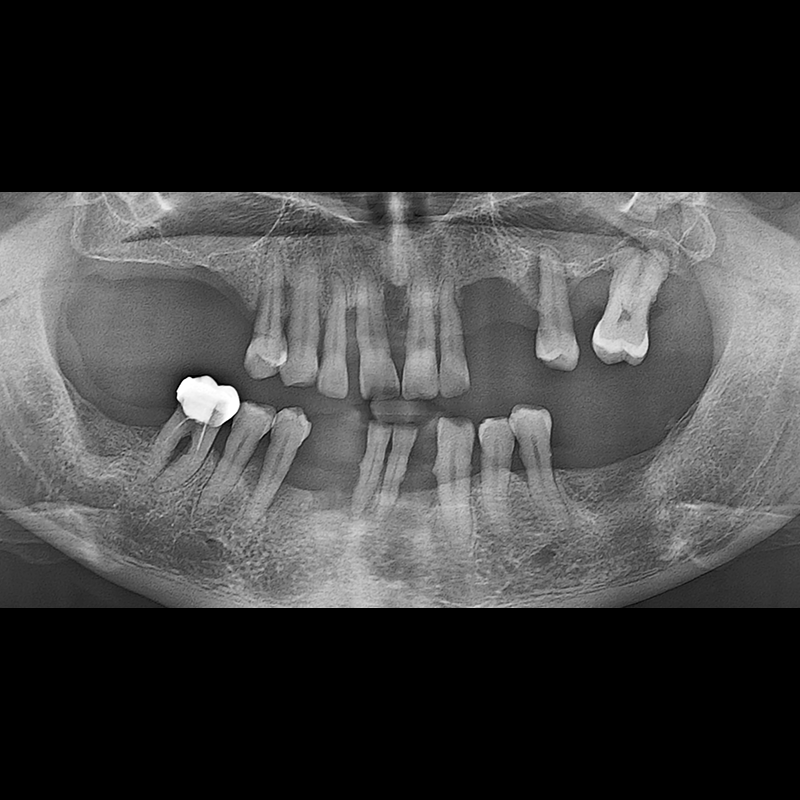

BEFORE AFTER

种植牙前后的照片 2025.05.30

在缺失的牙齿部分和难以挽救的牙齿位置植入了种植牙。